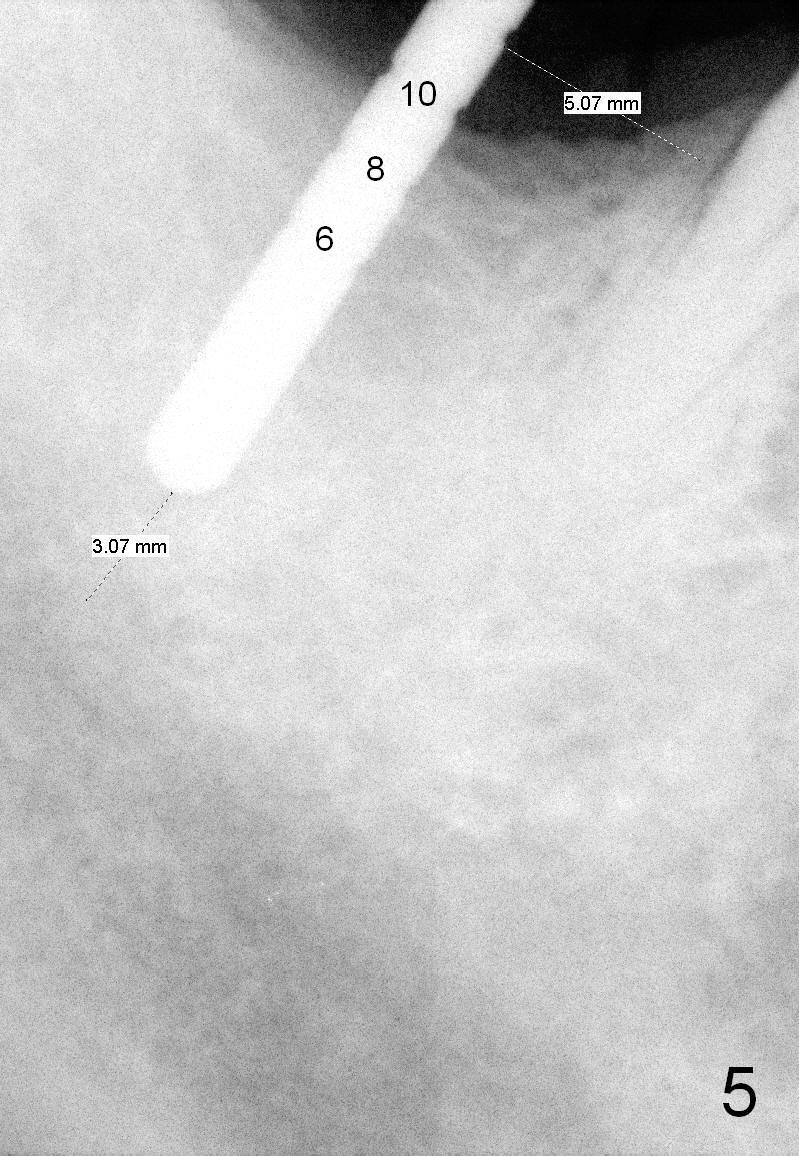

When a parallel pin is inserted with the depth of 10 mm, there is 3 mm from the superior border of the Inferior Alveolar Canal (Fig.5).